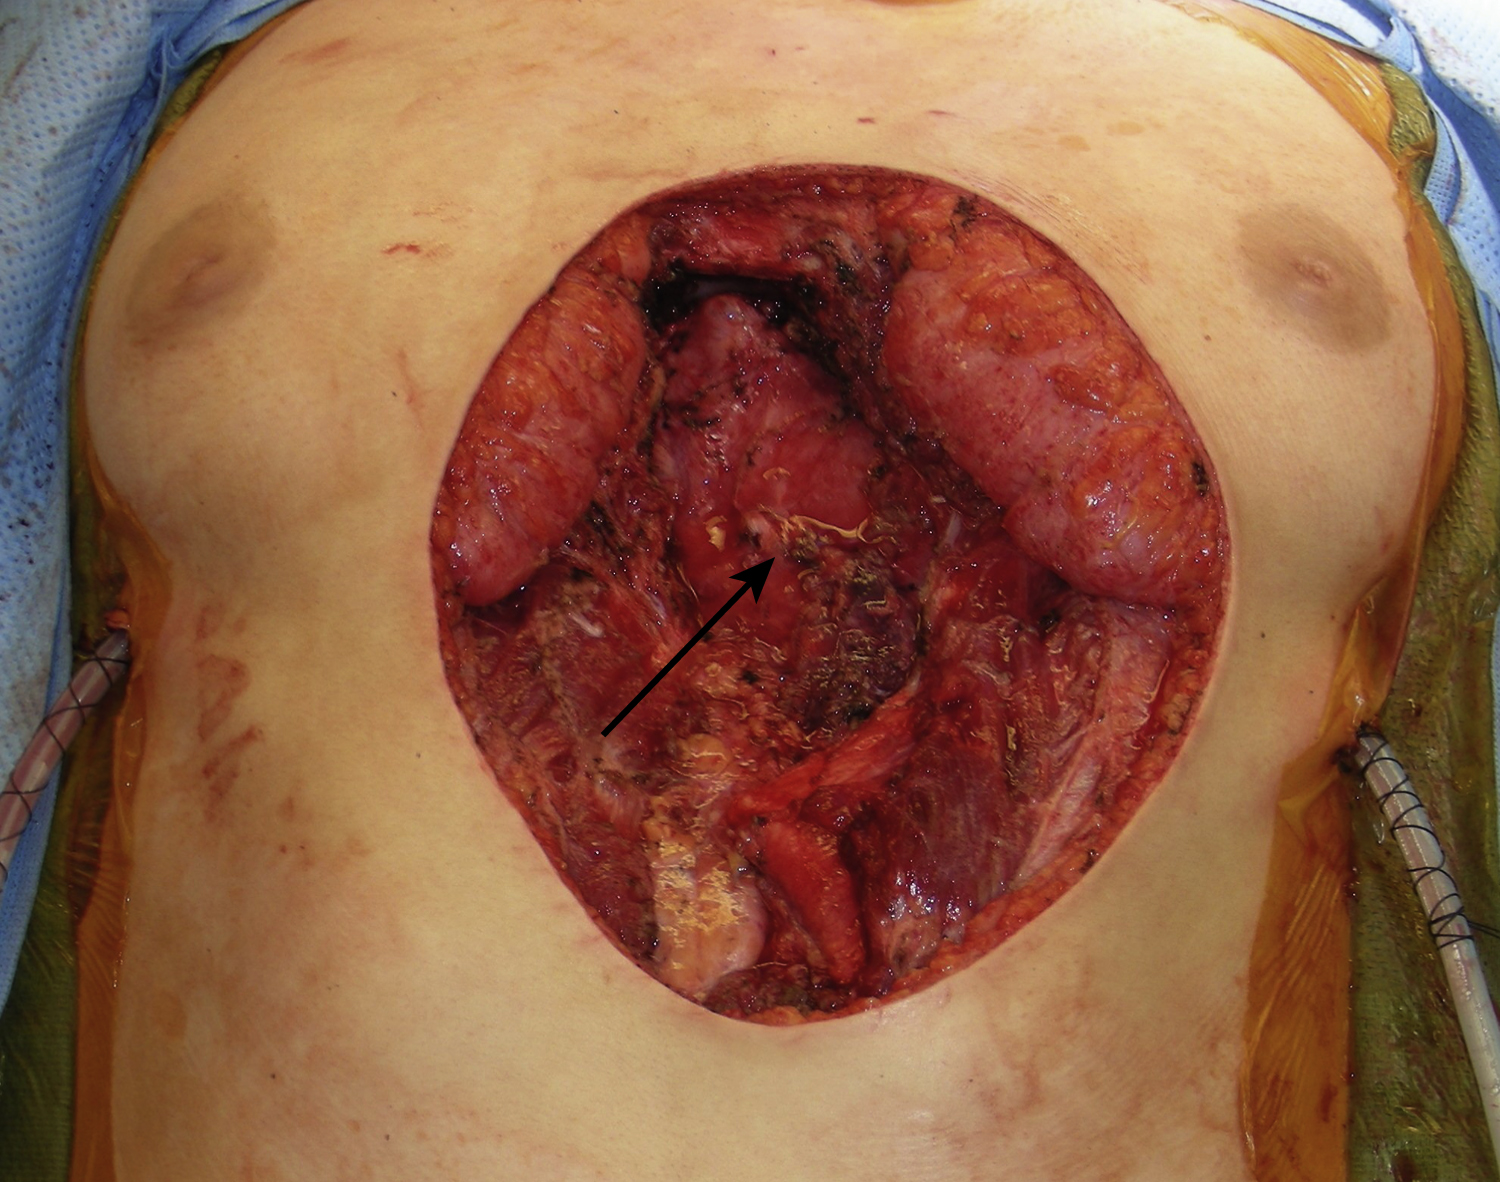

A 19-year-old White female had a large soft tissue mass in her lower chest and sternal area. Preoperative biopsy showed desmoid type of fibromatosis. She underwent resection of this soft tissue mass by the pediatric cardiothoracic surgery service and the plastic surgery service was asked to provide lower chest wall reconstruction after the tumor resection. After resection, the entire skin defect of the lower sternal and upper abdominal areas measured 18 × 14 cm to the rectus abdominis muscles on both sides. Both sides of the anterior rectus sheath were also resected ( Fig. 23.1 ). The lower sternal bony defect measured 13 × 6 cm ( Fig. 23.2 ). Two chest tubes were placed by the primary service. The left superior epigastric vessels were apparently transected during the resection. However, the right superior epigastric vessels remained intact.

Under general anesthesia with the patient in the supine position, the reconstructive procedure started after an adequate tumor resection. A 5-cm posterior rectus sheath defect over the upper abdomen was repaired with 2-0 PDS sutures in a figure-of-eight. The lower sternal bony defect, measuring 13 × 6 cm, was reconstructed with Strattice. The selected Strattice had several perforated holes. Scissors were used to prepare a 13 × 6 cm Strattice, which was placed onto the lower sternal bony defect while the dermal side was facing up, approximated with several interrupted 2-0 PDS sutures followed by 2-0 PDS sutures in simple running fashion ( Fig. 23.3 ).